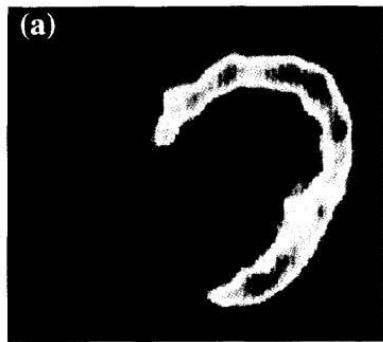

Fig 3. FDG-PET in the fasting state before and after 3 months of carvedilol therapy. (a) FDG uptake was enhanced throughout the left ventricle and (b) alleviated by carvedilol therapy. Figure 6: Taken from Hirooka et al. (151). Hirooka K, Yasumura Y, Ishida Y, Komamura K, Hanatani A, Nakatani S, et al. Improvement in Cardiac Function and Free Fatty Acid Metabolism in a Case of Dilated Cardiomyopathy with Cd36 Deficiency. Jpn Circ J (2000) 64(9): 731-5. doi: https://doi.org/10.1253/jcj.64.731. License granted

The complementary situation, i.e., diminished free fatty oxidation, can be found in patients with CD36 deficiency. Nishimura demonstrated that subjects with CD36 deficiency and cardiomyopathy had low BMIPP uptake. This defect could be corrected by the administration of $\mathrm{CoQ}_{10}$ using a dose of $30\mathrm{mg/d}$ for 35 days (152) (Figure 7).

Fig. 2. $^{123}\mathrm{I}$ BMIPP myocardial SPET images before and after Q10 treatment in a representative patient (case 3) with idiopathic dilated cardiomyopathy Figure 7: Taken from Kim et al.(152). Therapeutic Effect of Co-Enzyme Q10 on Idiopathic Dilated Cardiomyopathy: Assessment by Iodine-123 Labelled 15-(P-Iodophenyl)-3(R,S)- Methylpentadecanoic Acid Myocardial Single-Photon Emission Tomography. European journal of nuclear medicine (1997) 24(6): 629-34. Epub 1997/06/01. License CCBY. https://doi.org/10.1007/bf00841400.